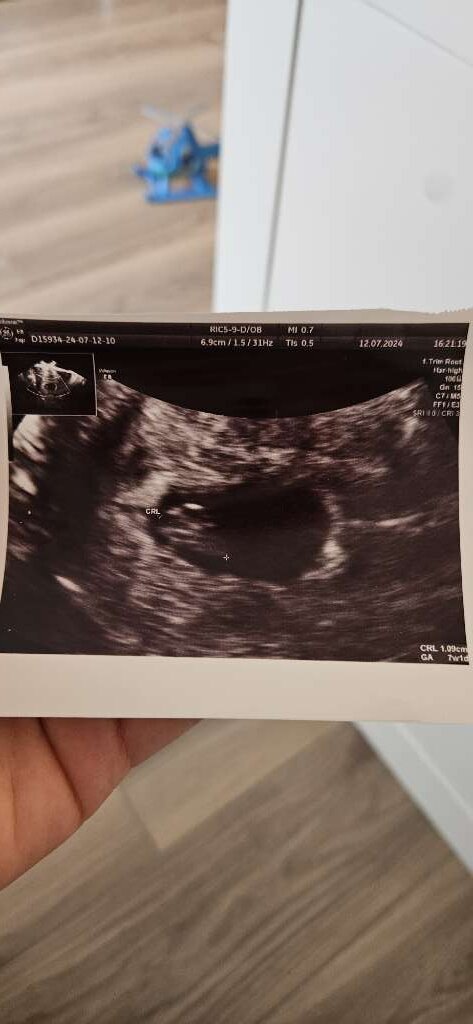

Całe 6,9 cm malucha, ciąża wygląda na młodszą o kilka dni, więc lekarz z TP chce się wstrzymać do USG pierwszego trymestru. Tak poza tym serduszko bije i wszystko jest na ten moment dobrze 🙂

Załączniki

• 6127fff3-2766-46fd-8ccd-c92ed9425879.jpeg

6127fff3-2766-46fd-8ccd-c92ed9425879.jpeg

53,9 KB · Wyświetleń: 83